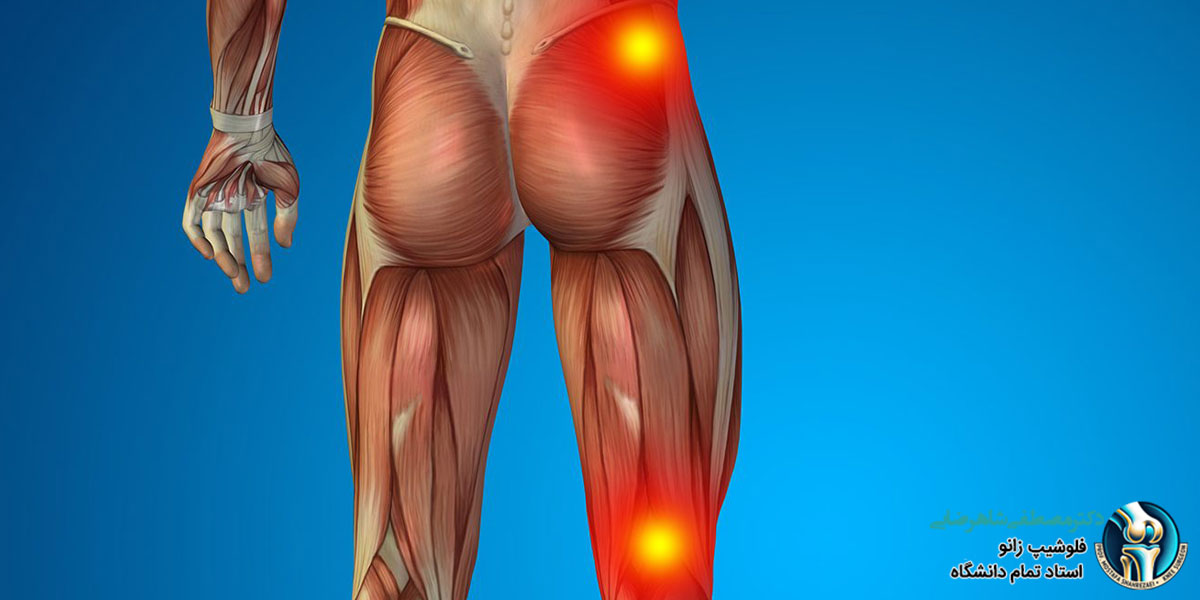

بررسی آناتومی و فیزیولوژی عصب سیاتیک عصب سیاتیک بزرگترین و طولانیترین عصب در بدن انسان است. این عصب از پیوستن چندین ریشه عصبی در ناحیه کمر تشکیل میشود و از آنجا به سمت پایین بدن حرکت میکند و در نهایت به پاها میرسد. عصب سیاتیک نقش بسیار مهمی در انتقال سیگنالهای حسی و حرکتی بین نخاع و عضلات و پوست اندام تحتانی دارد. عصب سیاتیک از پیوستن ریشههای عصبی L4، L5، S1، S2 و S3 در ناحیه کمر تشکیل میشود. این عصب از سوراخ سیاتیک بزرگ خارج شده و از پشت مفصل ران عبور میکند. سپس به دو شاخه تقسیم میشود که یکی به سمت پشت ران و دیگری به سمت پشت ساق پا حرکت میکند. عصب سیاتیک به عضلات بزرگ و کوچک ناحیه پشت ران، ساق پا و پا عصبدهی میکند. همچنین، این عصب پوست قسمتهایی از باسن، پشت ران، ساق پا و کف پا را حس میکند.

عصب سیاتیک، بزرگترین و طولانیترین عصب بدن، از ستون فقرات شروع شده و از پشت ران تا پایین پا امتداد مییابد. این عصب به عضلات و پوست بخشهای مختلف پا، از جمله زانو، عصبدهی میکند. هرگونه فشار، التهاب یا آسیب به عصب سیاتیک میتواند باعث ایجاد درد در هر نقطهای از مسیر این عصب، از جمله زانو شود. دلایل ایجاد درد زانو در سیاتیک عبارت است از: